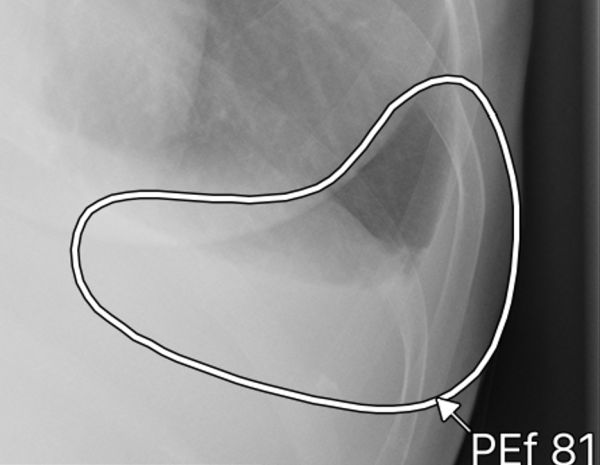

ヒートマップ/輪郭表示機能

異常所見の存在可能性(確信度)を、青から赤へのグラデーションで示すヒートマップ表示について、多くの利用者からご好評いただいている。一方、モノクロモニタを利用する一部の読影環境では、淡いヒートマップが確認しにくいという課題があった。新バージョンでは、異常所見の疑われる領域の表示方法として、「ヒートマップ表示」「輪郭表示」「ヒートマップと輪郭の併用表示」の3つの表示パターンが選択可能になった。これにより、各施設の運用環境に応じた最適な表示方法を利用できる。

また、従来のバージョンでは、対象所見が重なった領域においてヒートマップが重なって表示されていまた。そのため、異なる所見が混在している部分の識別が難しく、細かな判別や詳細な確認には限界があった。これに対し、新バージョンでは、対象所見が重なった領域についても、各所見ごとに独立した輪郭線を表示できるようになった。複数の異常所見が存在する箇所でも、それぞれの所見の範囲を明確に区別できるようになり、より詳細かつ正確な画像診断支援が期待される。